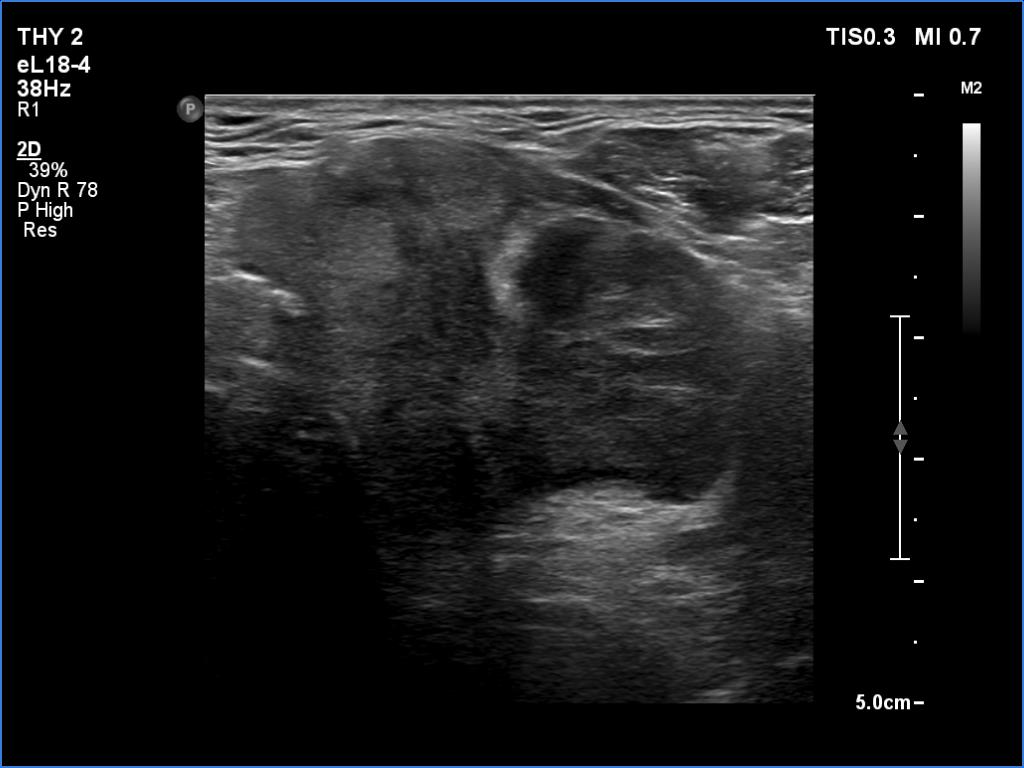

Ultrasonography. The right lobe was echonormal and intact. A large mass occupied almost the entire left lobe. On this side, normal thyroid tissue could only be identified in the dorsal part. The mass was composed of echonormal and hypoechoic areas, had macrocalcifications, irregular intranodular vascularity and proved to be very hard on elastography. There were multiple lymph nodes in III, IV and V left neck compartments. One of the nodes was in close proximity to the jugular vein and was suspicious of having broken into the vessel. The trachea was significantly narrowed at the lower level of the thyroid.

2. There are several remarkable findings in this case, e.g., the destruction of the left lobe by the tumor, the elastography pattern, the relation of the largest metastatic lymph node and the jugular vein, the ultrasound demonstration of the trachea' stricture.